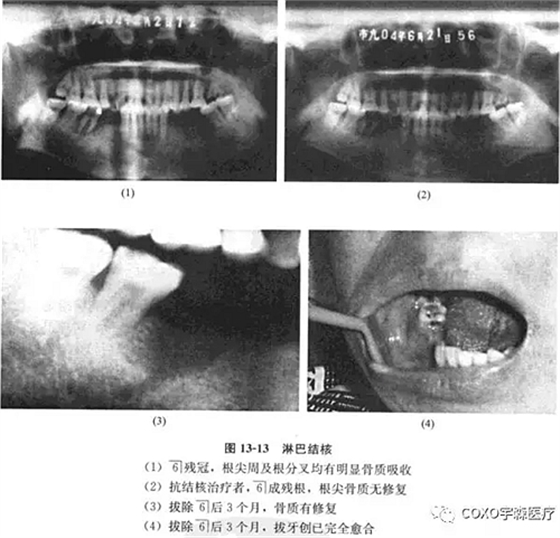

檢查:7-3]牙齦腫脹,54]缺失,6]呈殘冠狀,近中齦有炎性肉芽組織。x線片示:6]殘冠,根尖周及根分叉均有明顯骨質(zhì)吸收,雙頜下淋巴結(jié)腫大,質(zhì)中偏硬,臨床診斷為6]根尖周炎,頜下淋巴結(jié)核可能。

經(jīng)右頜下淋巴結(jié)穿刺,見(jiàn)上皮細(xì)胞、多核巨細(xì)胞和淋巴細(xì)胞,結(jié)合臨床及6]近中原切片,認(rèn)為病變符合結(jié)核診斷。行抗結(jié)核治療,3個(gè)月后復(fù)查,臨床頜下淋巴結(jié)顯著縮小,口內(nèi)牙齦腫脹基本消失,無(wú)任何創(chuàng)面,殘冠已折斷,僅剩6]殘根,X線示根尖周骨質(zhì)無(wú)修復(fù)現(xiàn)象。遂拔除司殘根,繼續(xù)行抗結(jié)核治療,3個(gè)月后骨質(zhì)有修復(fù),拔牙創(chuàng)已完全愈合(圖13-13)。

結(jié)核病可出現(xiàn)在口腔軟組織,也可以出現(xiàn)在頜骨組織內(nèi),臨床不多見(jiàn)。結(jié)核病出現(xiàn)在軟組織時(shí)可表現(xiàn)為潛穴性潰瘍,疼痛癥狀十分顯著。本病例最初表現(xiàn)為牙痛及牙齦腫塊,6]為死髓牙, 線片示根尖骨質(zhì)有吸收,牙齦組織切片僅提示結(jié)核可疑;后經(jīng)下頜下淋巴穿吸活檢6]區(qū)病損亦確認(rèn)為結(jié)核。經(jīng)抗結(jié)核治療后逐步好轉(zhuǎn),口內(nèi)腫脹消失,拔除6]后骨質(zhì)也逐漸得以修復(fù)。

本病例十分不典型,無(wú)疼痛癥狀;局部又存在死髓牙,極易誤診為根尖周病。其最后診斷依賴(lài)于下頜下淋巴結(jié)病理檢查,提示在診治根尖周病時(shí)必須進(jìn)行全面的口腔頜面部檢查而不僅僅限于牙及牙槽部。

本例6]根尖周病由殘冠引發(fā),局部伴發(fā)結(jié)核,髓腔通道可能是感染途徑之一。綜上所述,根尖周疾病的鑒別診斷,除特殊情況外,一般也并不困難,關(guān)鍵是: